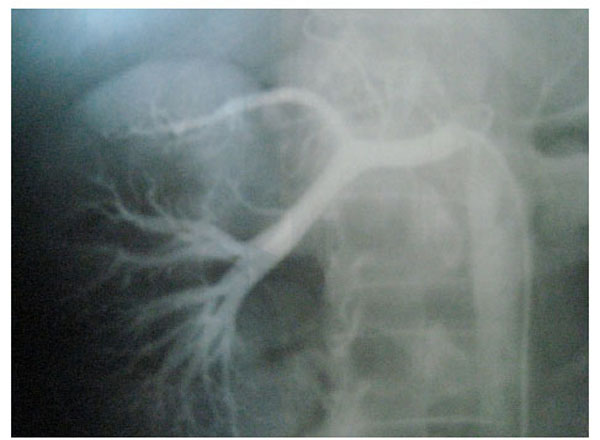

Fig. (3), Fig. (4), Fig. (5), Fig. (6), show images before and after systemic fibrinolytic treatment of two different patients, one suffering from partial emboli occlusion of main renal artery and the other, multiple segmentary intrarenal emboli.

Fig. (6).

Emboli lysis after fibrinolytic treatment with partial recuperation of perfusion of the parenchyma.